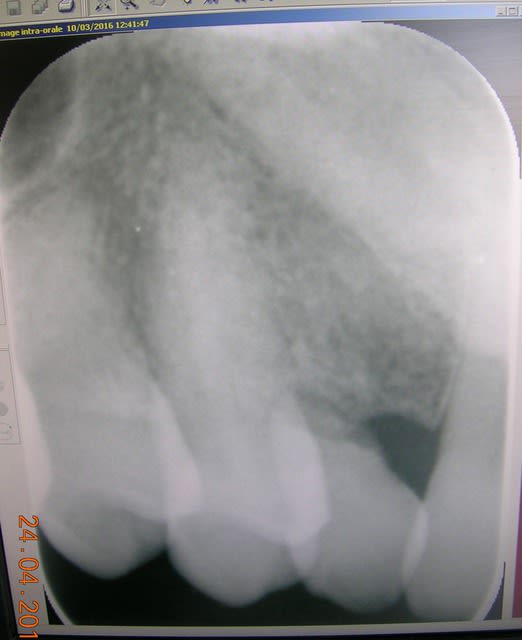

Cas clinique qui me pose problème.

Patiente 50 ans avec 53 en fin de parcours, quel serait votre plan de traitement?

Avec le temps l'espace mésio-distal 12 14 s'est nettement réduit (3 mms).

La 13 est incluse

La patiente ne veut pas d'ortho

1-la solution implantaire me parait compliquée vu le peu d'espace entre 12 et 14 et la présence de la 13 incluse.

2-solution d'un bridge collé avec une occlusion peu favorable

3-solution d'un bridge conventionnel......pas glop!!!

4-solution amovible.............pas glop, pas glop!!!!

Je suis un peu démuni devant ce cas pour lequel il faut trouver une solution rapide, la 53 ne tient quasiment plus.